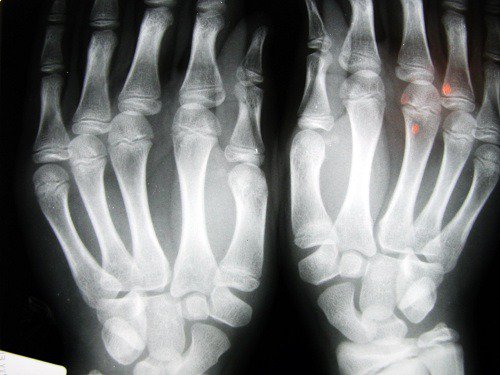

2. Risk of osteoarthritis